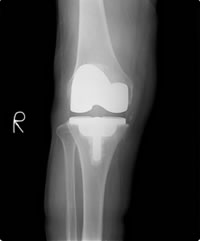

これに対して、人工膝関節置換術後(グラフ 青の実線、および図5)は、正常と完全に同じとまではいきませんが、歩行中のグラフの山が大小二つ認められ関節の動きが回復していることがわかります。これはきれいに歩けているだけではなく、関節にかかる負担が軽減したことを示します。

図4.重度変形性膝関節症 図5.人工膝関節置換術後

図5.人工膝関節置換術後三次元動作解析の限界